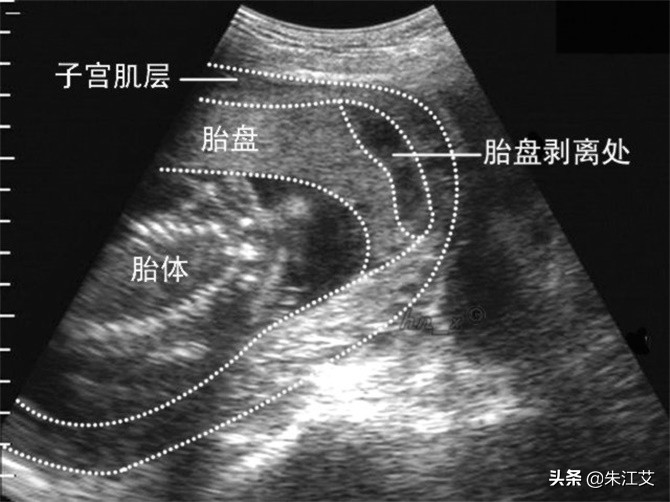

2. 胎盘早剥出血

1)一般存在胎盘早剥的情况都伴随着出血,根据剥脱的位置不同出血情况也不同。。

2)胎盘早剥容易发生在孕晚期。但是要注意一般出现胎盘早剥往往是因为孕妈肚子受到撞击,磕碰,跌倒等情况引起的。